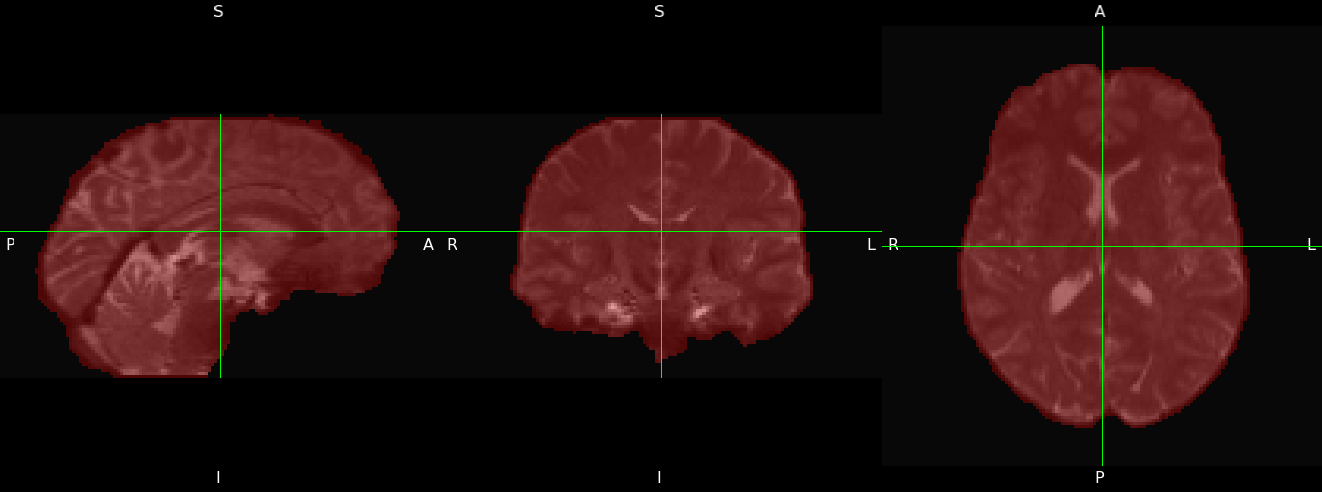

First, use fslmaths to combine the AP and PA outputs of topup into one file. the -Tmean option tells fslmaths to take the mean across time, resulting in a 3D dataset (one volume) named hifi_nodif (high fidelity, no diffusion). Then, that volume will be input into bet (Brain Extraction Tool) to create a brain mask.

fslmaths topup_AP_PA_b0_iout -Tmean hifi_nodif \

bet hifi_nodif hifi_nodif_brain -m -f 0.2